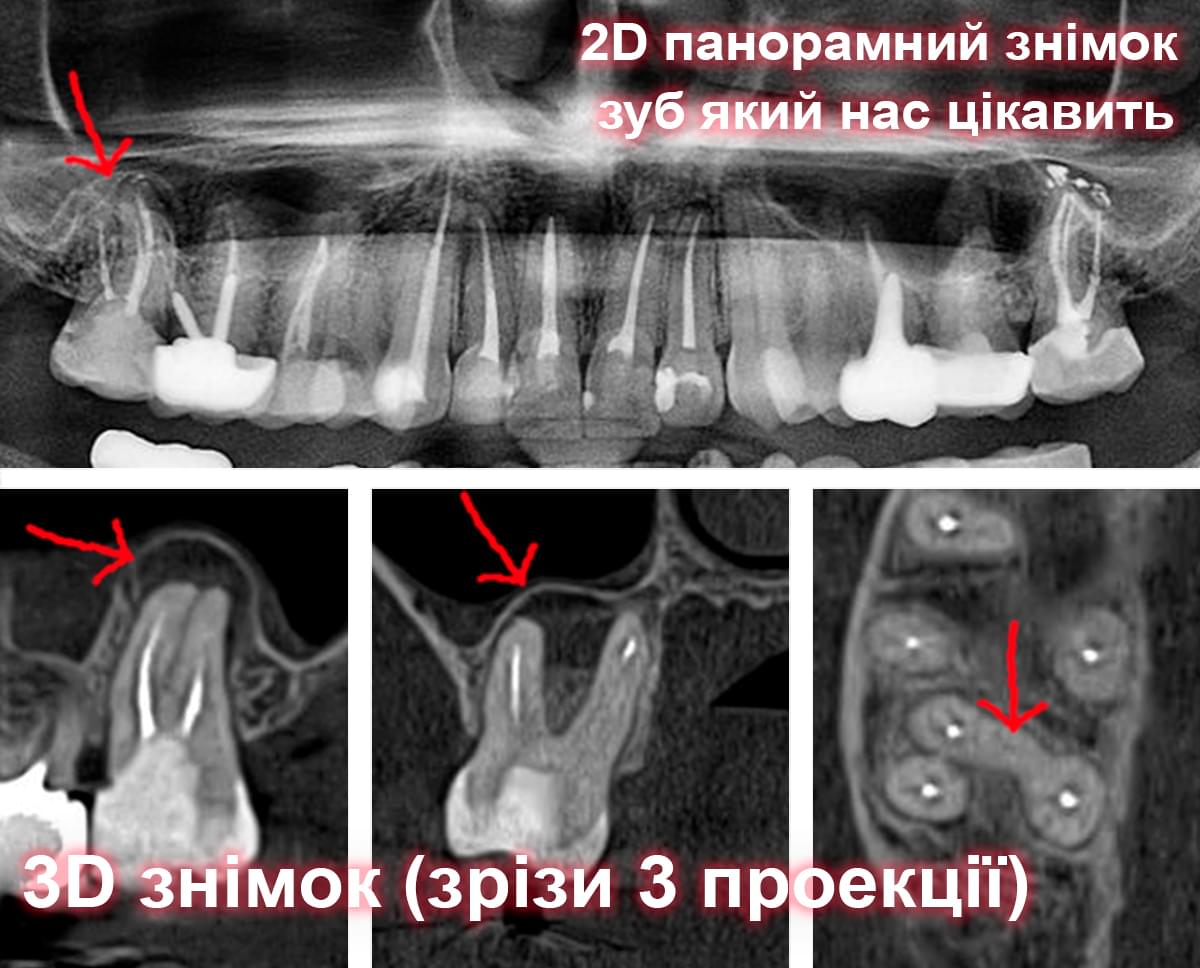

Візуальне порівняння (Кейс одного пацієнта)

Зуб — це не просто монолітний об'єкт, а складна система мікроканалів. На плоскому 2D-знімку вони часто перекривають один одного, створюючи ілюзію простої анатомії.

Непомічений канал — це джерело майбутньої інфекції та причина «загадкового» болю після лікування. Завдяки високій роздільній здатності обладнання MyRay, лікар бачить кожен мікронний канал ще до того, як візьме до рук інструмент.

Коли коріння «ховає сюрпризи» - Корені зубів часто мають складну кривизну, гачкоподібні закручення або розгалуження, які на звичайному 2D-знімку накладаються один на одного, створюючи ілюзію прямого каналу. На плоскій картинці неможливо побачити реальний об'єм та напрямок вигину, що критично важливо при видаленні «зубів мудрості» або ендодонтичному лікуванні. КТ MyRay дає змогу лікарю заздалегідь побачити 3D-геометрію кожного кореня, оцінити його близькість до нижньощелепного нерва чи гайморової пазухи та підібрати правильну тактику роботи. Це мінімізує ризики поломки інструменту в каналі або травмування сусідніх структур, перетворюючи складну хірургію на прогнозовану процедуру.